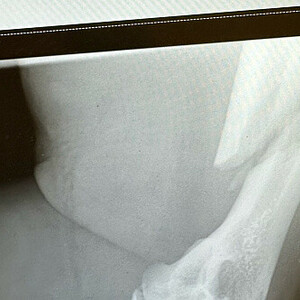

На турнире «Армафайт» в Рязани известный бодибилдер Андрей Попов получил тяжелую травму руки во время поединка по армрестлингу. Видео с соревнований появилось в соцсети.

О травме узнал сразу весь зал - по характерному щелчку. При этом рука спортсмена также приняла неестественную кривизну.

Выяснилось, что Андрей Попов получил сложный винтовой перелом руки. Его оперировали три часа.